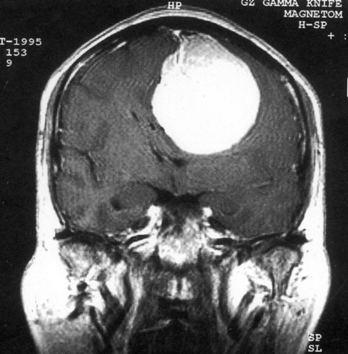

问题 病历摘要:??患者,男,40岁。发作性左下肢抽搐1年余,每次发作3~5分,每周发作1~2次。每次发作后感左下肢乏力,约半日后可自行恢复。既往身体健康。体检:神清,头顶部偏右有局限性骨性隆起(1.5×1.5cm),左鼻唇沟稍浅,伸舌居中。感觉、运动无明显异常。左浅反射减退,左下肢腱反射稍亢进,左Babinski征(-)。 根据病史、MR结果,考虑哪种诊断?提示:头颅?MR检查(见图)

选项 A.右顶叶星形细胞瘤 B.右顶叶转移瘤 C.脑膜瘤 D.右顶叶淋巴瘤 E.右顶叶少枝胶质细胞瘤 F.脑脓肿 G.右顶叶炎性肉芽肿

答案 C